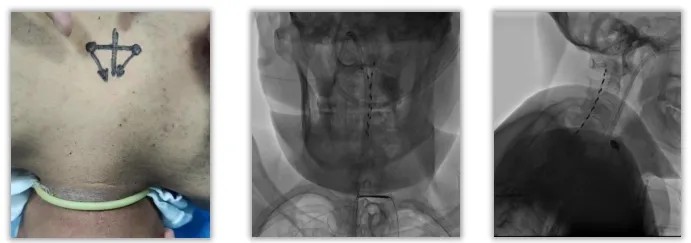

查阅大量文献,经过团队详细的讨论、评估,患者处于微小意识状态,可行脊髓电刺激手术,对病人的促醒有很大帮助。

脊髓电刺激原理:通过在颈髓C2-C4水平硬膜外放置刺激电极,脉冲刺激经上行网状激活系统传至大脑皮质,增加脑供血及大脑的局部葡萄糖代谢率,促进兴奋性递质的释放,增强意识冲动及脑电活动。

术中:全程在C臂透视下,当穿刺针到达椎板边缘时,取出针芯。连接无阻力注射器,继续推进穿刺针,直到出现“落空感”,即表示进入硬膜外腔。X光透视下,旋转穿刺针,确保斜边开口处朝向头部。在高颈髓、中线附近、硬膜外放置两条刺激电极。

电极植入C2-C4,选择尽可能高的触点(0-1+)做刺激,更容易刺激到脑干,激活上行网状激活系统;兴奋副交感神经,舒张血管,增加脑部供血。

刺激参数的选择:5Hz, 210μs, 开5min关15min, 刺激幅度达到上肢出现轻微抽搐为准, 仅在白天刺激;可以间接激活上行网状激活系统,既能增加脑血流(CBF)和脑代谢,又能诱发肌肉被动运动。